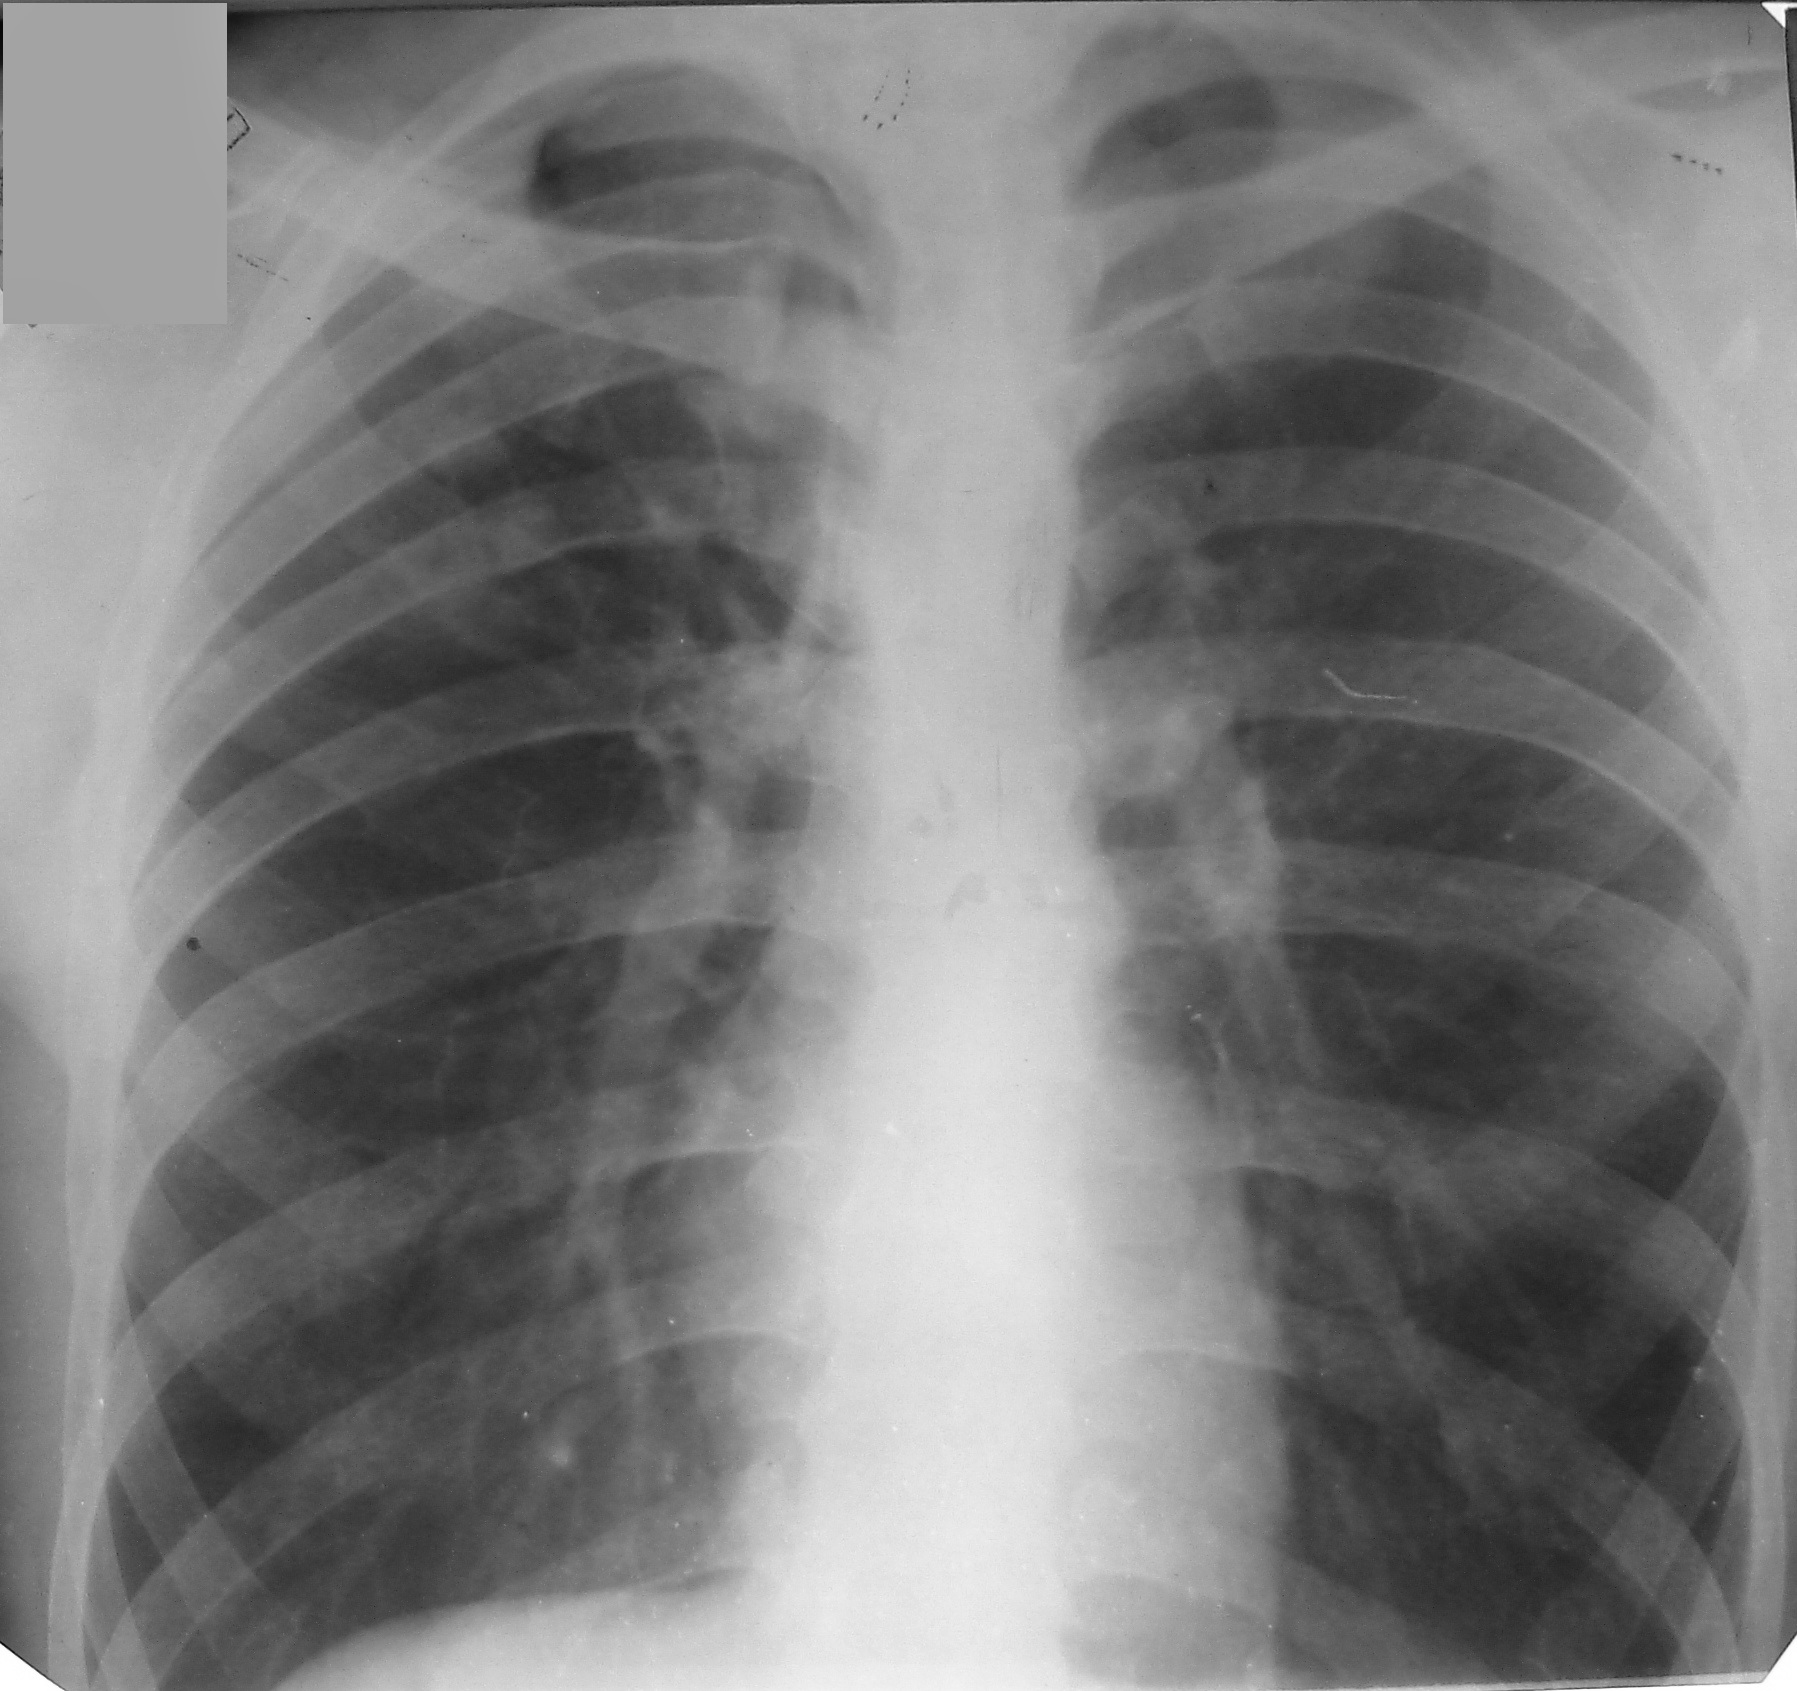

Что такое малоконтрастная рентгенограмма органов грудной клетки